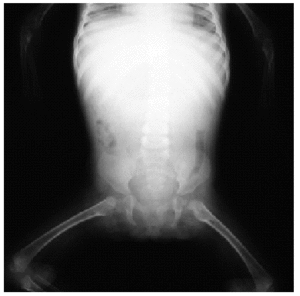

En el estudio complementario realizado que incluyó analítica completa, pruebas inmunológicas, niveles de aminoácidos y de mucopolisacáridos y pruebas serológicas para sífilis, citomegalovirus, toxoplasma y rubéola fueron normales. El cariotipo también fue normal y en el estudio radiológico se revelaron quistes osteolíticos en la parte proximal de ambos fémures y múltiples contracturas en flexión de las articulaciones con un aumento de la densidad de partes blandas periarticulares que les hacía radiológicamente visibles (figs. 3 y 4). El estudio histopatológico de una lesión tumoral puso de manifiesto una importante papilomatosis con una dermis papilar engrosada y una matriz eosinofílica hialina PAS+ sobre las que existen células de hábito fibroblástico (figs. 5 y 6). Existe una ausencia de tinción para fibras elásticas y un leve infiltrado inflamatorio linfocitario rodeando a algunos ductus.

Fig. 4.--Estudio radiológico que muestra quistes osteolíticos en la parte proximal de ambos fémures.